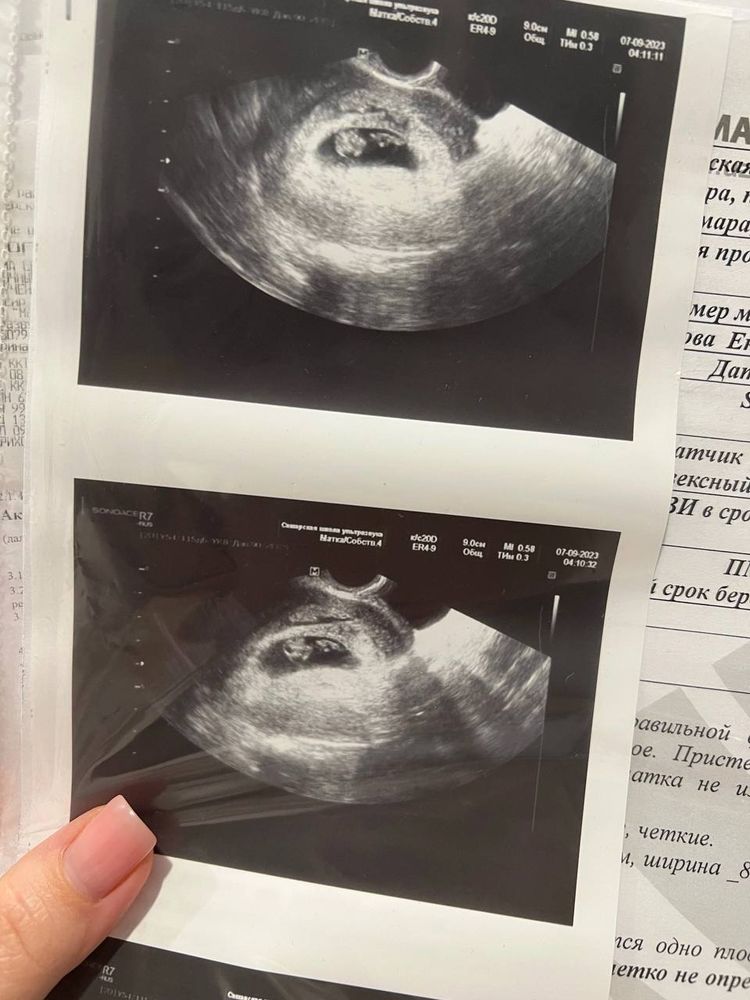

По идее гематома - это скопление крови после того как от ложился кусочек хориона/плодного яйца от стенки матки. То есть, по определению гематома будет рядом с плодным яйцом, а не внутри него. Я бы скорее сказала, что это второй эмбрион.

Екатерина Галдина, и я того же мнения🙏🏻 но в таком случае странно, что при таком размере у него до сих пор нет сердцебиения

Ого, о таком я ещё не слышала. Почитаю. Вроде как даже если бы это был второй эмбрион и он замер, на маленьком сроке он вреда второму не принесёт, просто рассосётся или мумифицируемая Для меня главное, чтобы это было не что-то опасное. Врач в жк напугала гематомой, но я почитала и ни одного признака гематомы у себя не нашла. Да и выглядит она по-другому

Катя, да, гематома обычно рядом с плодным яйцом и выглядит она как темная полоска. Возможно малышок второй еще маленький и сб скоро появится, всякое бывает. В любом случае желаю вам чтобы все сложилось максимально удачно! 🙏🌸